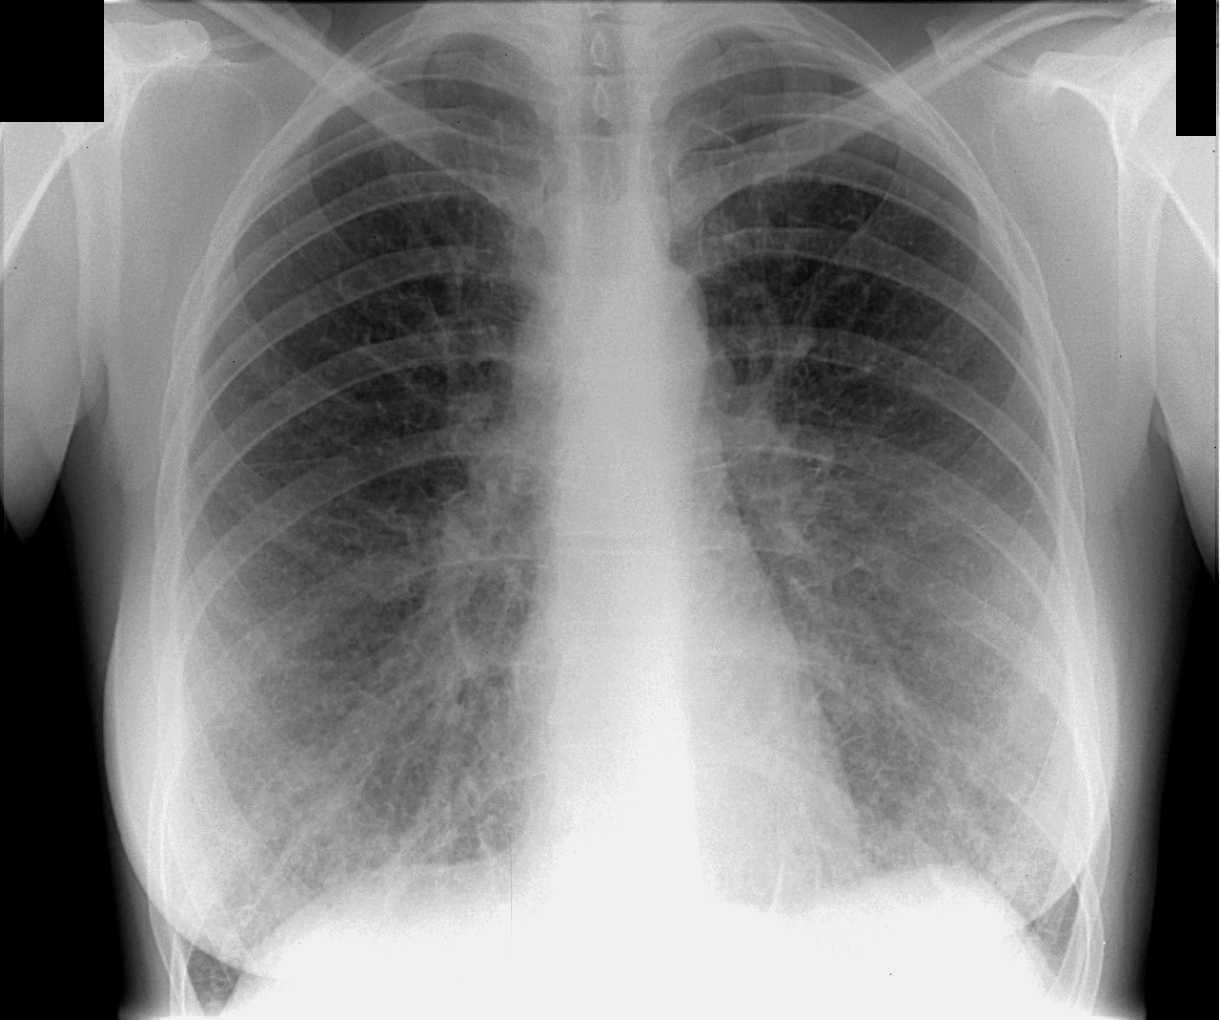

Нормальная рентгенограмма легких: что нужно знать

Раздел: Мудрость в объективе